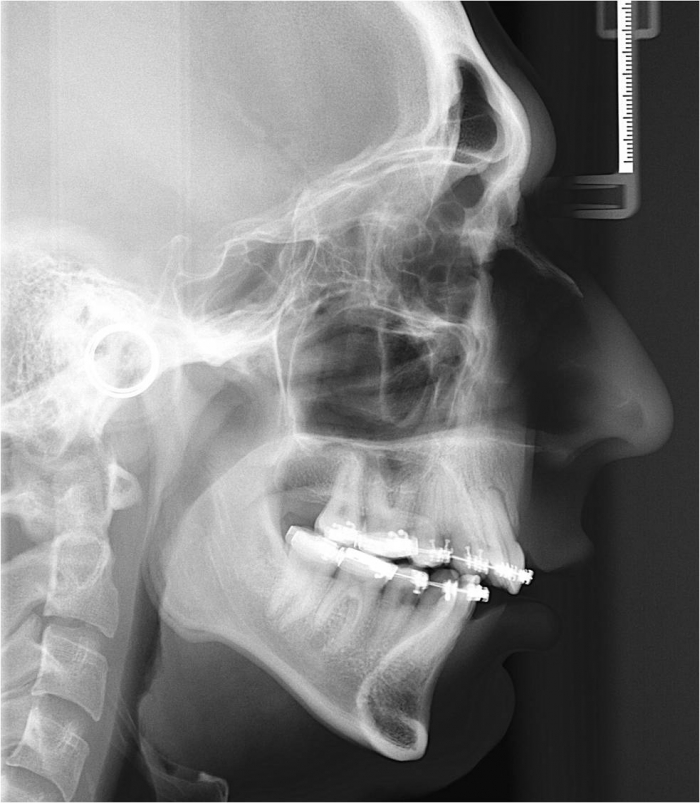

Raio x após a cirurgia

Telerradiografia após a cirurgia